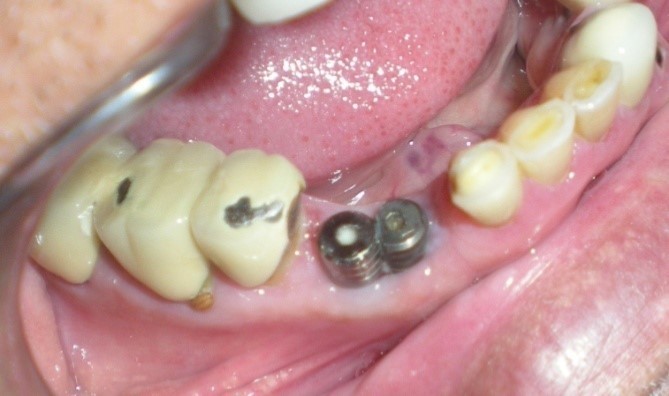

Healing abutments were cleaned and removed from mouth (Figure 2) and placed in a disinfecting solution. Direct impression coping (AlphaBio, Israel) was on one of the implants (SPI, AlphaBio, Israel) and secure it with long connecting screw (Figure 3).

Figure 2.Modified healing abutment in position.